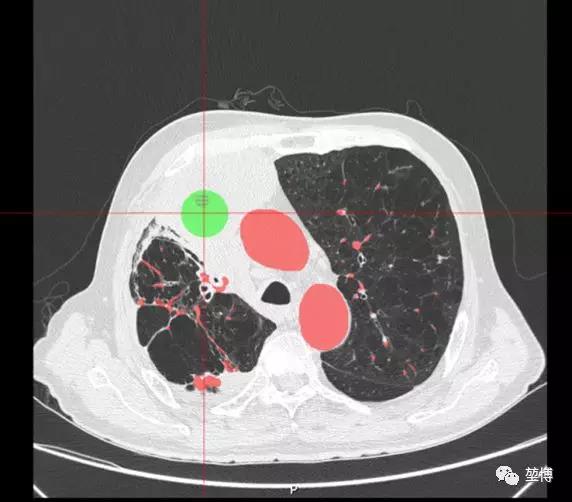

患者病灶位于右上叶前段,病灶大小约77mm*67mm*59mm,病灶较大,由于患者已是癌症晚期,出现多发转移,不具备手术指征,因此考虑姑息性治疗。龙主任结合病情拟LungPro导航引导下行BTPNA肺部肿瘤微创介入治疗——激光消融治疗。

如上图所示,该患者病灶有明显气道相通,但气道紧挨病灶边缘,单纯气道内消融无法抵达病灶中央,达到最大的消融治疗效果,因此选择内外结合法——气道内消融+气道外消融。拟在LungPro导航引导下行BTPNA术,直接抵达病灶中心,随后进行气道外消融。

气道内消融预测范围

气道外消融预测范围